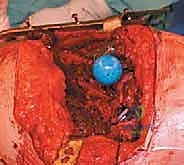

- الاستخراج المعقد (Implant Removal): يتم فتح المفصل بحذر شديد لحماية الأنسجة المتبقية. يقوم الدكتور هطيف باستخدام أدوات جراحية دقيقة ومتخصصة لإزالة المفصل الصناعي القديم (الساق المعدنية، الكوب الحُقي، والمسامير). التحدي هنا هو إزالة هذه الأجزاء دون التسبب في كسور إضافية للعظم الذي قد يكون هشاً بسبب العدوى.

- التنظيف الجراحي الجذري (Radical Debridement): هذه هي أهم خطوة في العملية بأكملها. يتم استئصال جميع الأنسجة الميتة، المصابة، والملتهبة. يتم كشط العظم حتى الوصول إلى نسيج عظمي حي ونازف. يستخدم الدكتور هطيف تقنيات الجراحة المجهرية الدقيقة للتأكد من عدم ترك أي خلية مريضة، مع الحفاظ على الأنسجة السليمة والأعصاب والأوعية الدموية. يتم غسل التجويف بلترات من المحاليل المعقمة والمطهرات الطبية.

- تشكيل ووضع المباعد الأسمنتي (Antibiotic-Loaded Cement Spacer): بعد التأكد من نظافة الحقل الجراحي، يقوم الجراح بخلط "أسمنت عظمي" طبي مع جرعات عالية جداً من المضادات الحيوية (يتم اختيارها بناءً على المزرعة البكتيرية السابقة).

- يتم تشكيل هذا الأسمنت ليأخذ شكل مفصل الورك المؤقت.

- وظيفة المباعد: يحافظ على طول الساق، يمنع انكماش العضلات المحيطة بالورك، والأهم من ذلك: يقوم بإفراز تركيزات عالية جداً من المضادات الحيوية مباشرة في مكان العدوى على مدار الساعة، وهو ما لا يمكن تحقيقه بالأدوية الفموية.

* المباعد الثابت (Static Spacer): كتلة صلبة تمنع الحركة تماماً، يُستخدم في حالات فقدان العظم الشديد.

* المباعد المتحرك (Articulating Spacer): يشبه المفصل الحقيقي ويسمح ببعض الحركة، وهو المفضل لدى الدكتور هطيف متى ما سمحت حالة العظام بذلك، لأنه يسهل إعادة التأهيل لاحقاً.

- إعادة بناء العظم (Bone Grafting): في كثير من الحالات، تكون العدوى قد دمرت أجزاء من عظام الحوض أو الفخذ. هنا تتجلى خبرة الدكتور هطيف في استخدام طعوم عظمية (إما من بنك العظام أو عظام صناعية) أو استخدام دعامات معدنية متقدمة (Augments و Cages) لتعويض العظم المفقود وبناء أساس قوي للمفصل الجديد.

- زراعة مفصل المراجعة المعقد (Revision Arthroplasty): المفاصل المستخدمة في هذه المرحلة تختلف عن المفاصل الأولية؛ فهي مصممة لتكون أطول، وأكثر استقراراً، وتحتوي على آليات تثبيت معقدة لتعويض ضعف العضلات والأربطة. يتم تثبيت الكوب الحُقي الجديد وساق الفخذ بدقة ميكانيكية حيوية فائقة لضمان عدم تعرض المريض للخلع مستقبلاً.